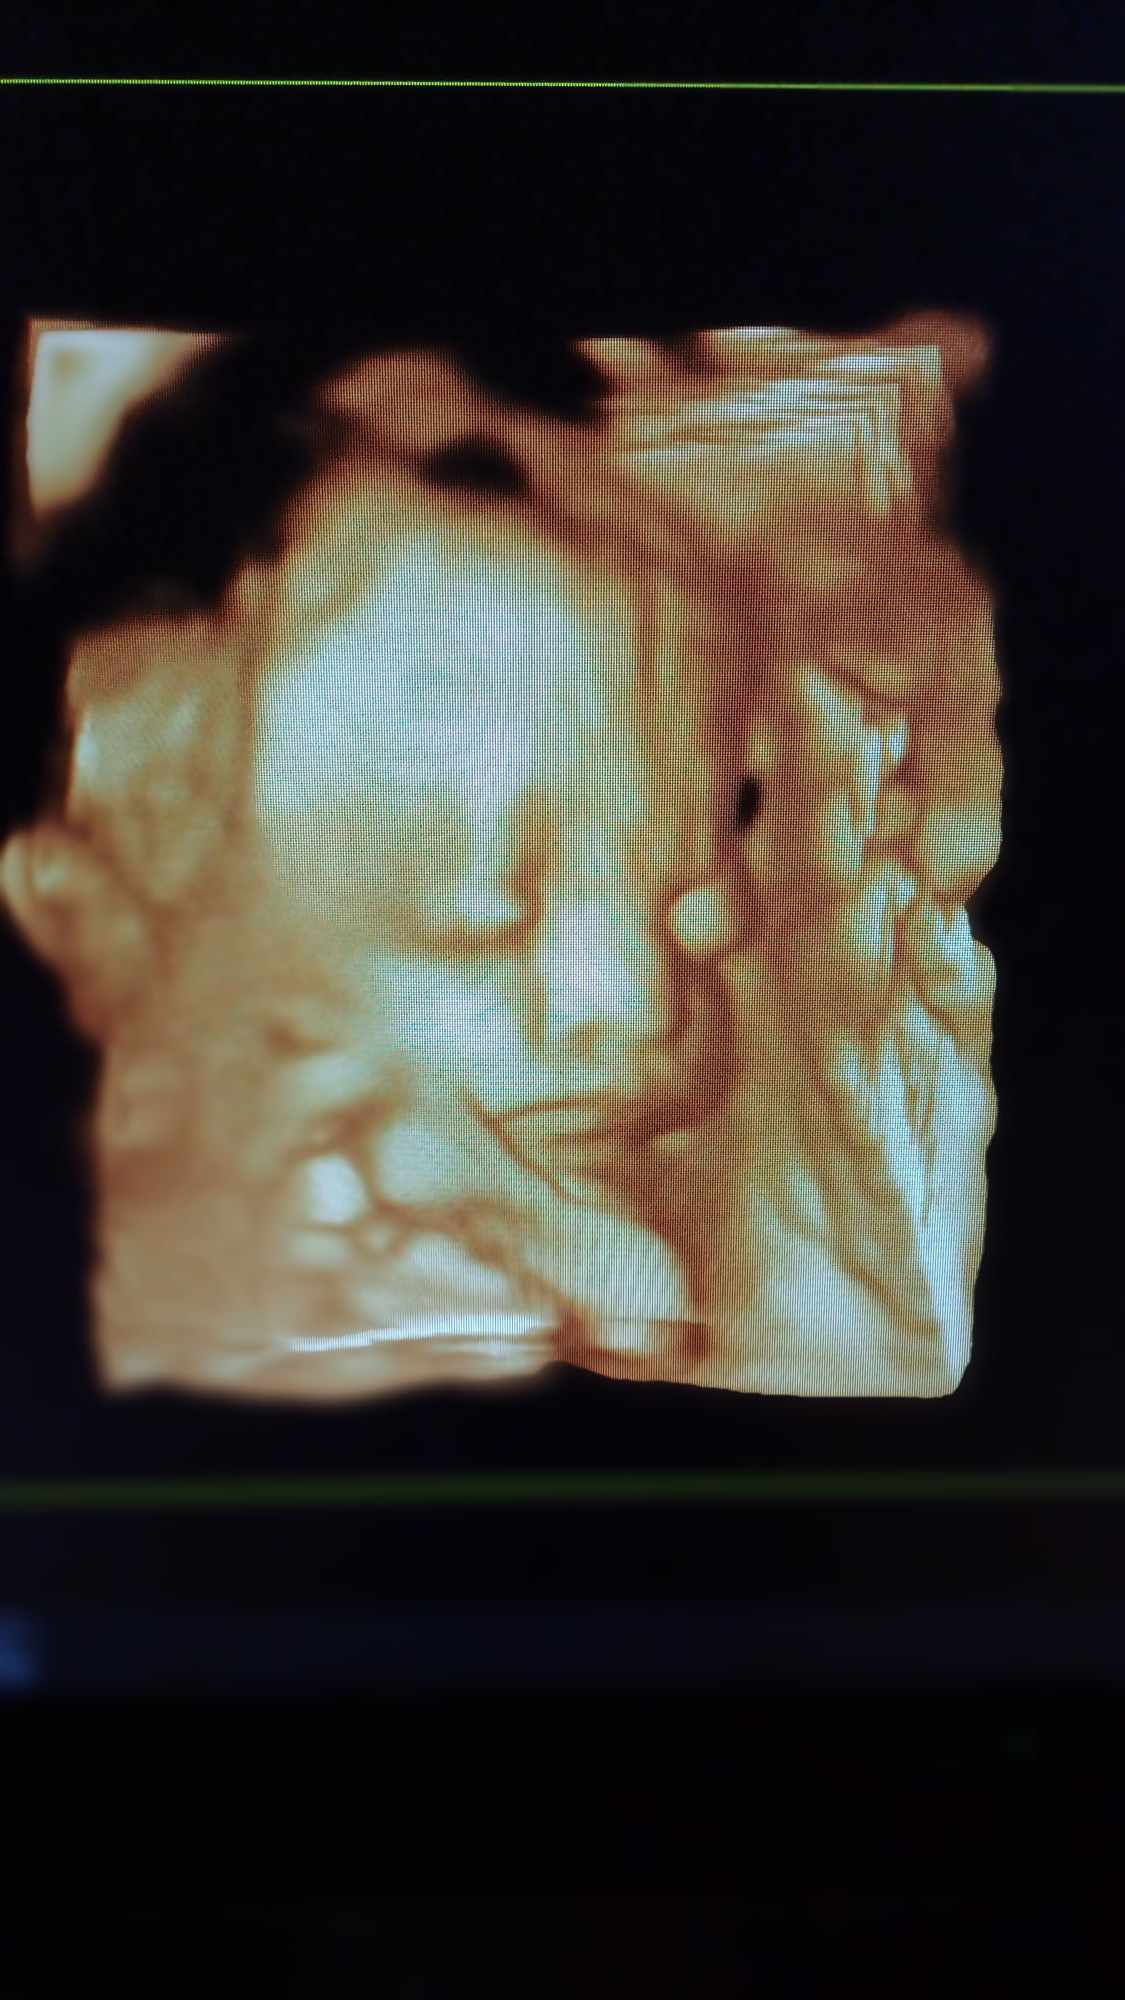

Pozrite si fotky z nášho moderného pracovného prostredia

Naša gynekologická ambulancia je vybavená modernou technikou a poskytuje pacientkom príjemné a komfortné prostredie pre všetky druhy vyšetrení a konzultácií.